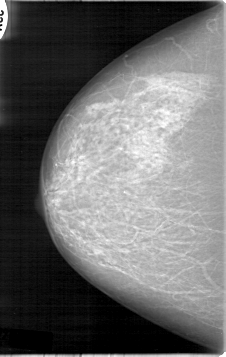

D_4014_1.RIGHT_MLO

RIGHT_CC LINES 5341 PIXELS_PER_LINE 3376 BITS_PER_PIXEL 12 RESOLUTION 43.5 NON_OVERLAY

RIGHT_MLO LINES 5281 PIXELS_PER_LINE 3721 BITS_PER_PIXEL 12 RESOLUTION 43.5 NON_OVERLAY